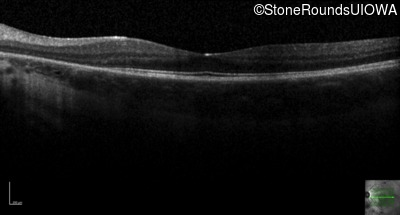

Optical Coherence Tomography - Right - 20/20 -1

Exemplar / OCT Stack

OCT Stack